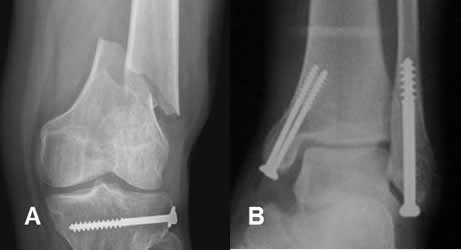

Fig 98. Tornillos de esponjosa.

A: Rx AP. Fractura espiroidea del fémur distal. Se encuentra tornillo de esponjosa en la tibia proximal (Solo roscado en la mitad distal), que fija fractura antigua.

B: Fractura bimaleolar, fijada con tornillos de esponjosa.